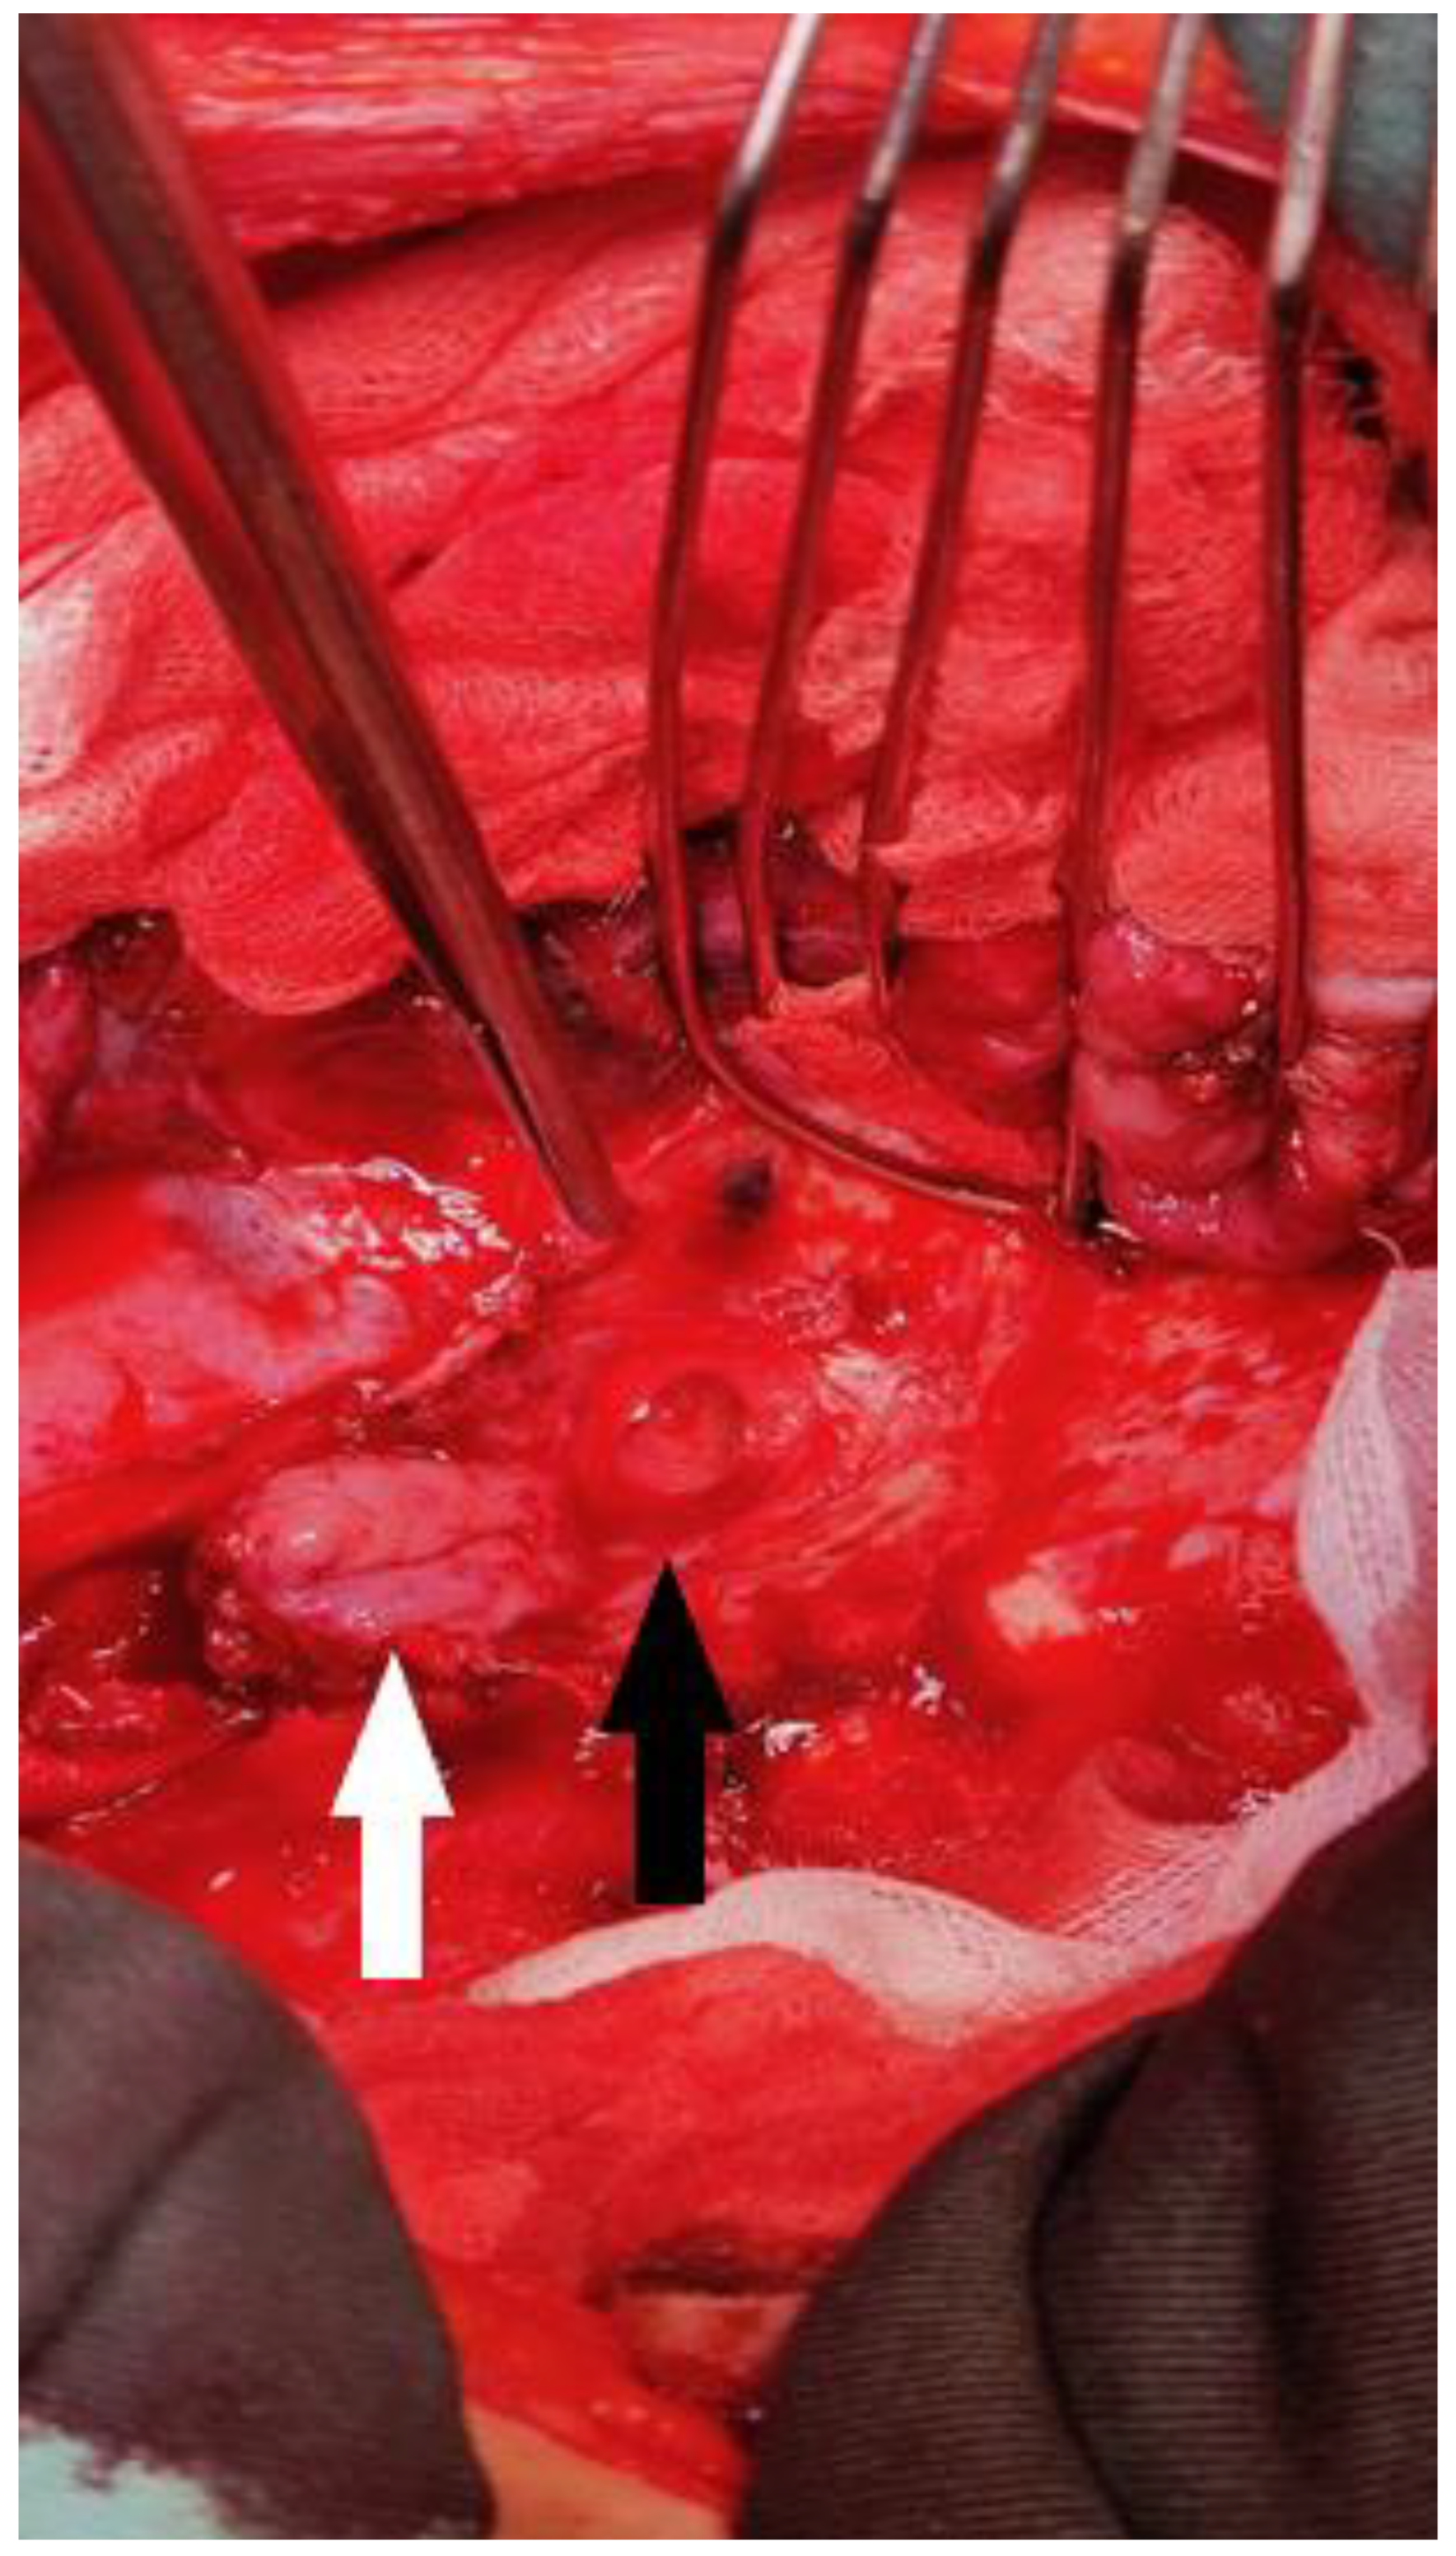

Subsequently, an esophagogram showed the leakage of the contrast medium into the tracheobronchial lumen, demonstrating the presence of a TBF (Figure 2). This was confirmed via MDCT and bronchoscopy. An NG tube was placed for feeding and decompression of the gastric conduit. Antibiotics meropenem (1 g, 8 h) and vancomycin (1 g, 12 h) were administered with the addition of parenteral nutrition.

Figure 2.

Contrast X-ray study showing the gastrobronchial leak. The diagnostic modalities include barium swallow, CT imaging, bronchoscopy, and upper gastrointestinal endoscopy. Identifying TEF can be challenging. Esophagoscopy can often miss small or discrete fistulas, even with fluoroscopy. Contrast radiography is a very useful method in terms of establishing this diagnosis. It is actually the confirmatory test for TEF. The appearance of barium in the lumen of the tracheobronchial tree is a direct sign of the fistulization of these structures within the esophagus. This picture shows a clear esophagobronchial leak, which provoked an irritating cough during the patient’s examination.